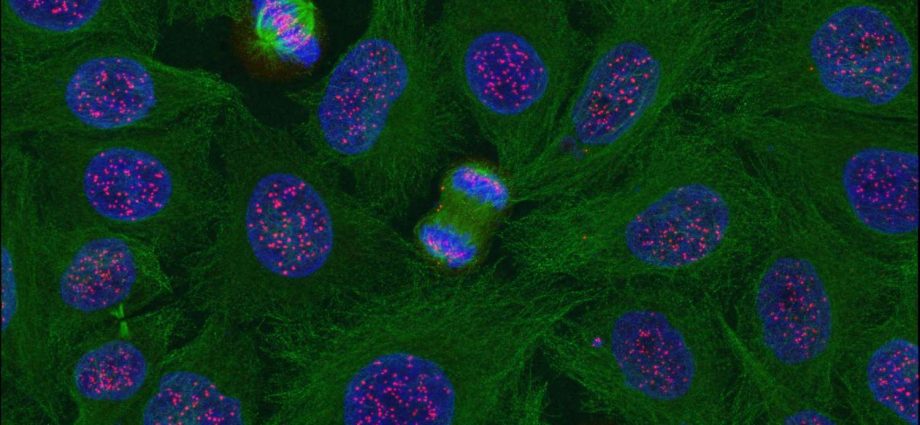

Le corps des êtres vivants tels que des animaux et des hommes possède une incroyable quantité de cellules, environ 100 000 milliards au total. Par conséquent, il est en état de renouvellement cellulaire permanent, à partir de la naissance jusqu’à la mort. Il est en quelque sorte constamment remis à neuf.

Pratiquement tous les organes, tous les tissus et toutes les cellules sont soumis à ce renouvellement cellulaire permanent et vont être complètement régénérés plusieurs fois dans une vie, à une fréquence plus ou moins élevée en fonction des cellules. Ce qui fait qu’au bout du compte, l’immense majorité des cellules et des organes sont plus jeunes que l’individu lui-même.

Ce vaste écosystème cellulaire – qui est finalement notre organisme – contient environ 250 types de cellules différentes. La grande majorité est soumise au renouvellement cellulaire, sauf quelques exceptions, comme, par exemple, les neurones et les cellules cardiaques où le renouvellement est très lent ou quasi inexistant.